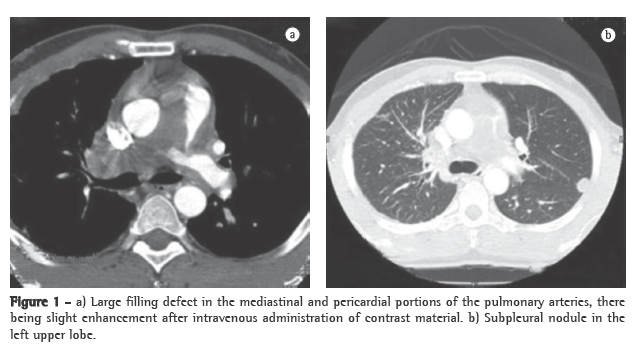

A transthoracic Doppler echocardiogram, which had been performed previously, showed moderate right heart enlargement, and pulmonary artery systolic pressure (PASP) was estimated to be 76 mmHg. A transesophageal echocardiogram demonstrated extensive thrombosis in the pulmonary artery trunk and PASP of 57 mmHg. Ultrasonography of the lower limbs revealed no signs of deep venous thrombosis. Lung perfusion scintigraphy, which was performed during hospitalization, showed low uptake in the view of the anterior and the apical-posterior segments of the left lung. The right lung was not visualized. Angiotomography of the chest revealed a large filling defect in the mediastinal and pericardial portion of the pulmonary trunk and arteries, there being enhancement of that defect after intravenous administration of contrast material (Figure 1a). In addition, there were predominantly peripheral nodules on the left (Figure 1b), as well as thickening of interlobular and peribronchovascular septa on the right, associated with upper lobe consolidation, moderate pericardial effusion and a mosaic attenuation pattern (Figure 2).

The clinical profile, together with the age of the patient, the failure of anticoagulant treatment, the tomographic alterations and the contrast enhancement, led to the hypothesis of intimal sarcoma-angiosarcoma-with pulmonary metastases. A CT-guided transthoracic biopsy of the left lung nodule was required. The specimen obtained consisted of a soft, reddish-tan filiform fragment, measuring 1.2 cm in length.

The case reported here draws attention to the need to raise the differential diagnosis in patients who are unresponsive to the current treatment of venous thromboembolism. Intimal sarcoma of the pulmonary artery is among the alternative diagnoses. Since iodinated contrast enhancement (angiotomography of the chest) can confirm the presence of the mass as well as its central location in the pulmonary trunk and arteries, which strongly suggest a diagnosis of intimal sarcoma of the pulmonary artery rather than that of CPTE, it constitutes a clue for making the former diagnosis. We emphasize the need for the proper use of the clinical methods currently available for the exact etiological definition of arterial pulmonary hypertension, prior to prescribing new medications (phosphodiesterase-5 inhibitors and inhibitors of endothelin receptors).(8,16)